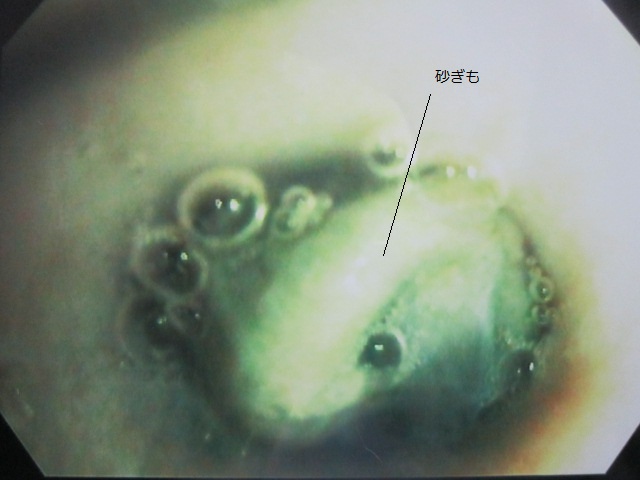

IMG_5041

内視鏡で砂ぎもを胃に押し込みました。

食道内に異物はなくなっています。